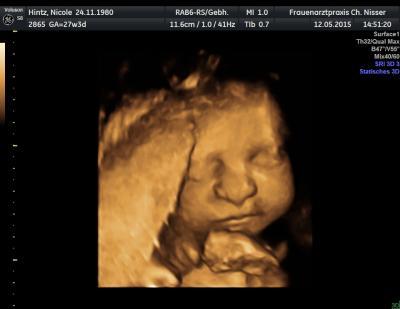

Gerade vom arzt rein.Gewicht vom Kind ca. 1160g, kein zucker, kein Eiweiß, CTG i.o., Eisenwert zu niedrig. Hab Eisentabletten bekommen und die Spritze wegen dem Rhesusfaktor. Mein Gewicht wie vor 2 Wochen. Blutdruck 130/90. Zur Zeit sieht alles supi aus. Keine Frühgeburtsbetrebungen oder Gestoseerscheinungen.

Bild zu Update Frauenarzt - Forum für August - Mamis

Schön das alles im Ordnung ist Und ein suuuper Bild würde ich auch gern haben wollen

Super Werte und tolles Bild

Wow du hast echt ein tolles Bild!